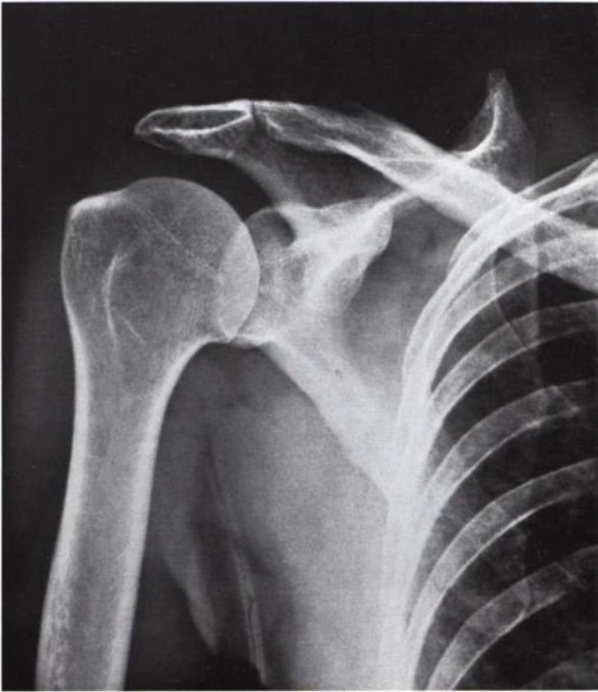

What is this view of the shoulder? what views are missing?

AP

MISSING:

AP internal rotation

AP external rotation

Axial

Scapular Y Shoulder

AC Joints (spot, weighted